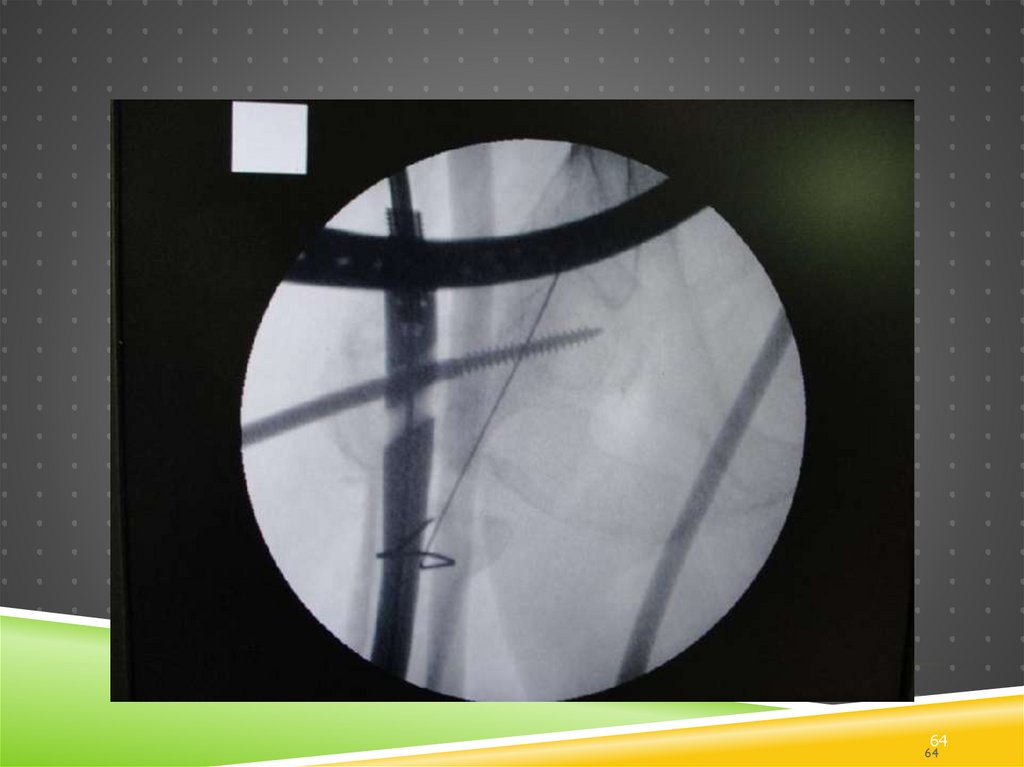

Дальше…

Спицы AP2

надо убрать

перед

сверлением

канала под

винт